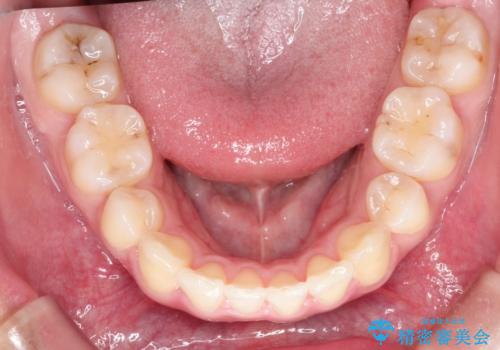

乳歯を抜歯することにより、通常よりは治療期間を要してしまいましが、前歯のガタガタもなくなりきれいな歯並びになったと喜んでいただけました。